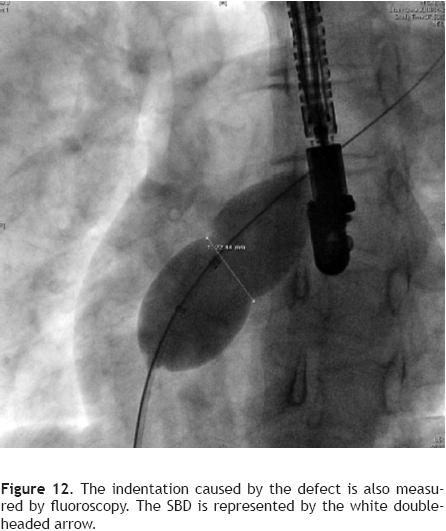

The diameter of the indentation can also be measured with fuoroscopy (Figure 12) using calibration markers on the balloon catheter. SBDs by both methods are compared and measurements are repeated if there is a greater than 1 mm discrepancy.22